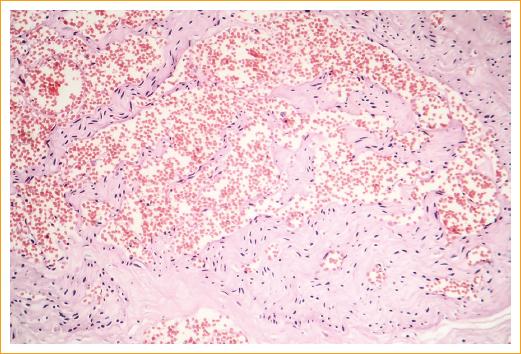

The histopathological characteristics of this vascular hamartoma varies depending on the clinical phase. In the early proliferative phase, the tumor consists mostly of endothelial cells, and vascular spaces are rare, likewise, it contains numerous mast cells. In more mature tumors, larger vascular spaces are observed, with a lower number of endothelial cells (Fig. 3). The tumor does not encapsulate and, generally, does not tend to infiltrate the surrounding structures. In the involutional phase there is often deposition of fibrous and adipose tissue around and inside the lesion3.